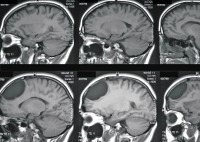

Fallbericht: Blickdiagnose "Arachnoidalzyste" erweist sich als Irrtum: akute Symptomatik einer 14 Jahre alten supratentoriellen endodermalen Zyste

Journal für Neurologie, Neurochirurgie und Psychiatrie 2015; 16 (4): 178-182 Volltext (PDF) Praxisrelevanz Abbildungen